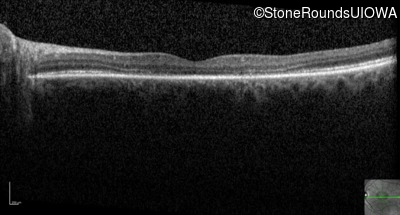

Optical Coherence Tomography - Right - 20/20

Exemplar / OCT Stack

Optical Coherence Tomography - Left - 20/100 -1